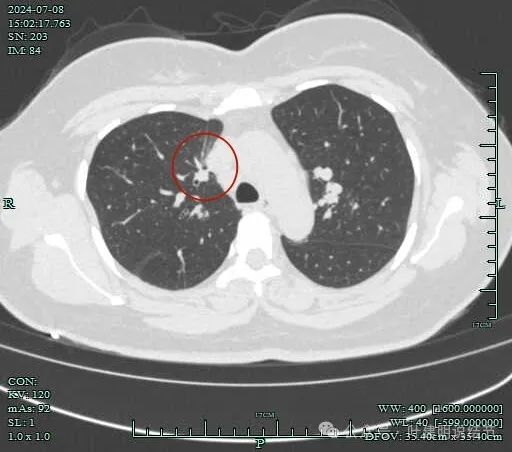

再看2024年7月份的影像:

病灶整体轮廓还是较为清楚的。

病灶边支气管可见。

病灶小,但有一定收缩感。

心缘旁另有实性小结节,像良性些。